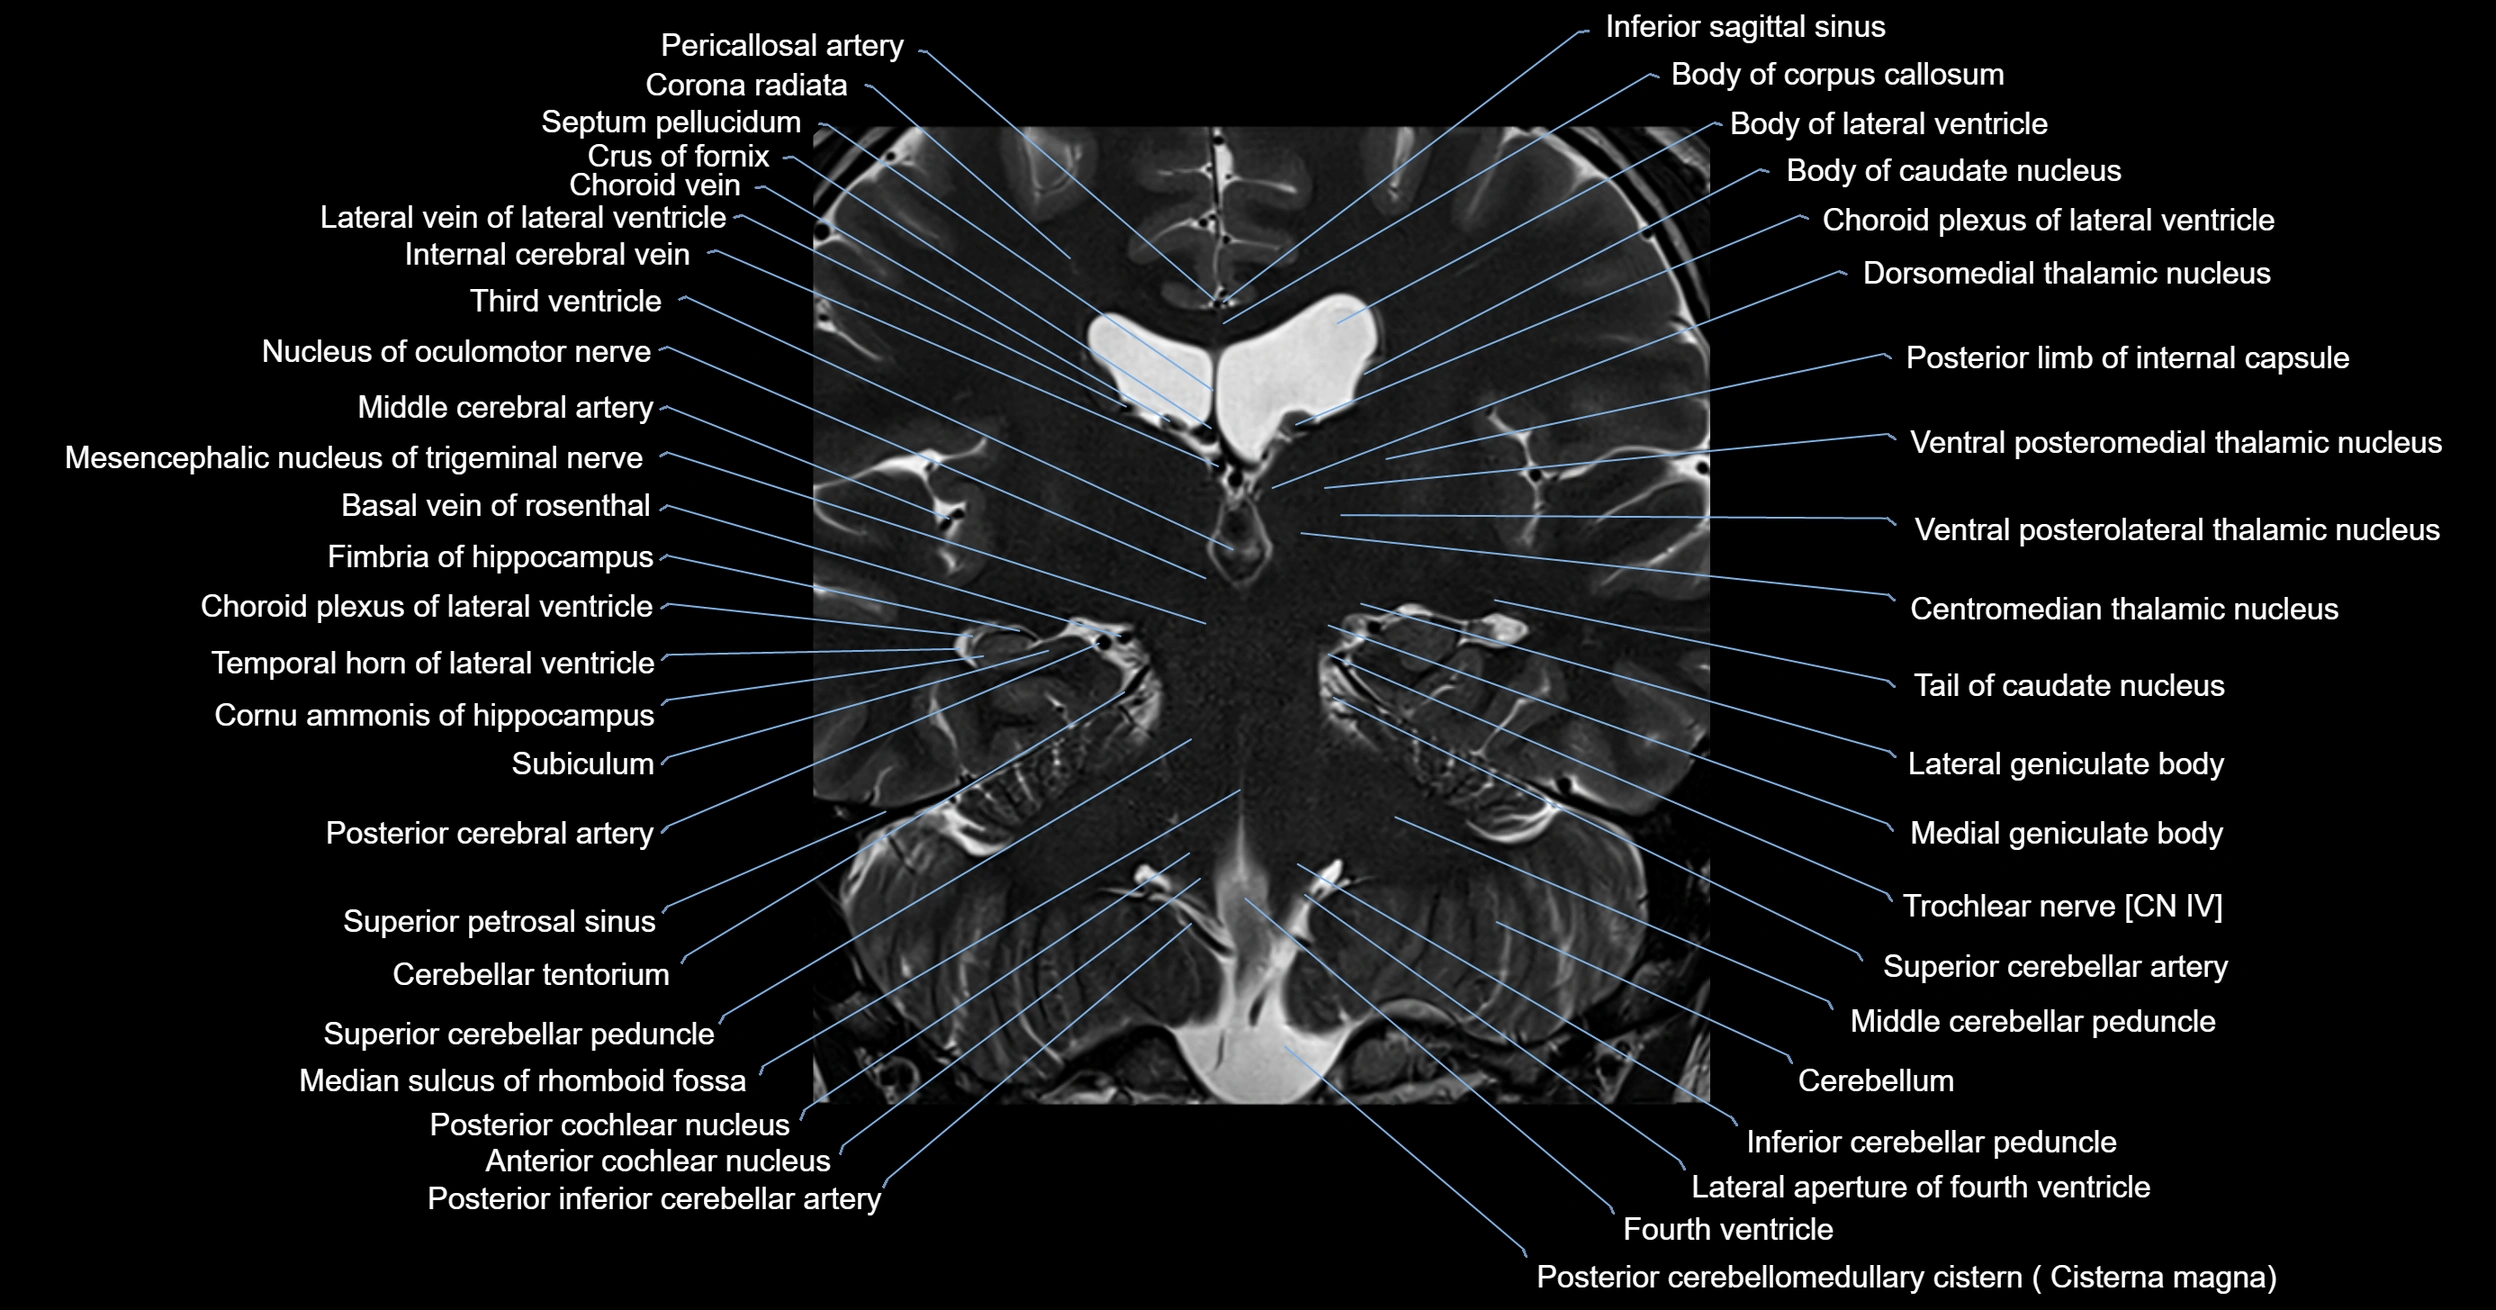

- Basal vein of rosenthal

- Cerebellum

- Crus of fornix

- Dentate nucleus

- Fourth ventricle

- Inferior cerebellar peduncle

- Internal cerebral vein

- Medial lemniscus

- Median sulcus of rhomboid fossa

- Middle cerebellar peduncle

- Posterior cochlear nucleus

- Superior cerebellar peduncle

- Tail of caudate nucleus

- Third ventricle